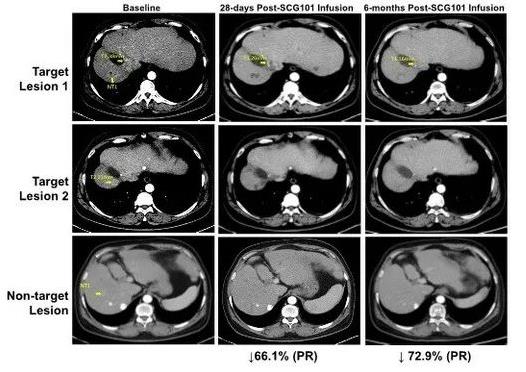

SCG101是一种乙肝抗原特异性的TCR-T细胞疗法,2022年3月,其新药IND获中国国家药品监督管理局(NMPA)批准。该产品的神奇之处在于可同时清除HBV感染细胞,以及HBV-DNA整合的癌前病变细胞、HBV-HCC肿瘤细胞,达到抗癌和抗病毒的双重功效!2023年在法国巴黎举行的国际细胞与基因治疗大会(ISCT)上,公布了SCG101治疗乙型肝炎病毒(HBV)相关肝细胞癌(HCC)的突破性临床数据。一位确诊HBV相关肝细胞癌的患者,在接受单剂SCG101治疗后,获得部分缓解(PR),在肿瘤病灶缩小的同时,HBV感染也得到缓解。

1、肿瘤病灶缩小:该患者在接受单剂SCG101输注后的第28天,肿瘤靶病灶比基线时缩小66%,更令人惊喜的是,在治疗第4个月时,病灶进一步缩小至74.5%;同时另一处病灶完全消失。截至数据截止时,该患者肿瘤未进展时间已超6.9个月。

图2 HBV相关肝细胞癌患者,在回输SCG101前后的影像学变化

▲图源“CISION”,版权归原作者所有,如无意中侵犯了知识产权,请联系我们删除